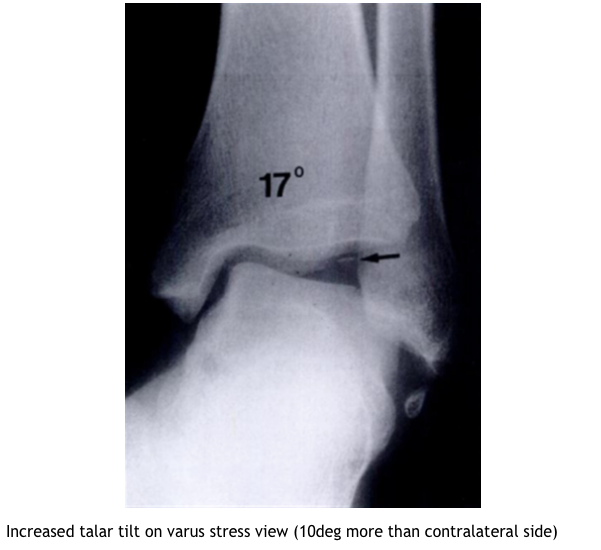

What imaging is helpful in Os Subfibulare?

What is DDX of Os Subfibulare?